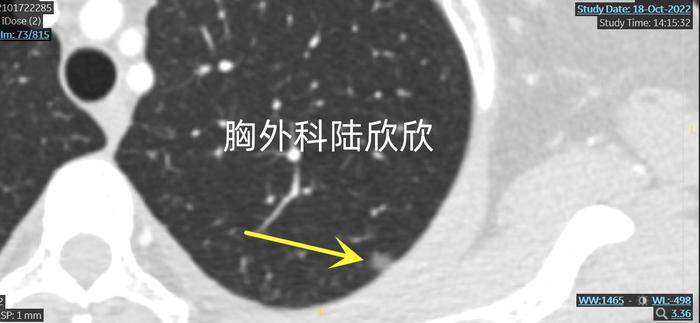

住院以后,进行了薄层CT检查。我们先看左下肺比较大的磨玻璃结节。

我们可以看到左下肺斜裂旁一个长方形的磨玻璃结节,中间密度比较低,像是一个窗户的框架

上图,这个较淡的纯磨玻璃结节最大径8.0毫米。我在门诊和病人说:“虽然其它医院的医生认为很可能是良性的病变。但是,我认为,这个结节基本上是恶性的磨玻璃结节。这个结节是由圆形或椭圆形的磨玻璃结节多年来缓慢转变来的。这种方框形的磨玻璃结节如果是恶性的,一般不像是原位癌,像是微小浸润性腺癌。”

手术做了定位后的胸腔镜下左下肺楔形切除术。最终的病理证实是微小浸润性腺癌,证实了我的判断。